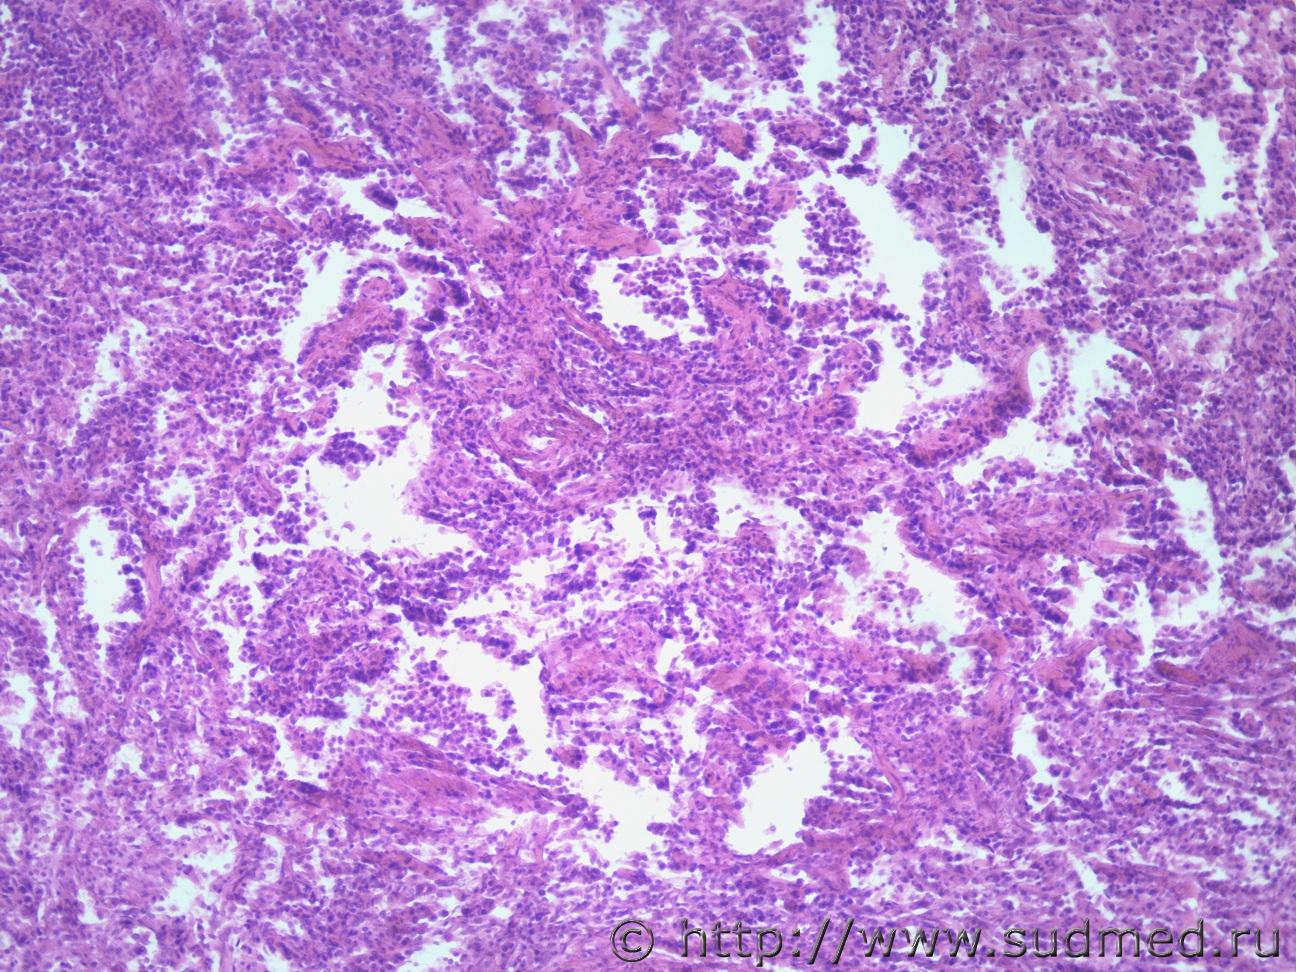

Жен 68 лет Нижняя доля легкого

Предположу бронхиолоальвеолярный.

кроме эпителиально-клеточной инфильтрации ввиде пневмоцитов 2-порядка с округлой центральной и эксцентричной локализацией ядер с зернисто-эозинофильной цитоплазмой, наблюдается мезенхимальные структуры в строме ввиде миофибробластических.